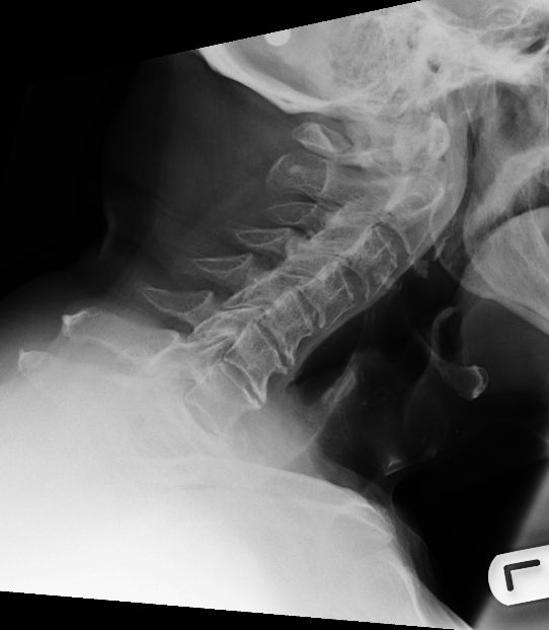

Odontoid Fracture X Ray View . evaluation of odontoid fractures. Common injuries to the upper cervical spine. odontoid fractures are relatively common fractures of the c2 (axis) dens that can be seen in low energy falls in elderly patients. The three types of odontoid fracture. there are many influencing factors leading to appropriate treatment of odontoid fractures such as age, bone. Type ii and type iii are unstable fractures. Fracture of c2 (dens) bimodal age distribution.